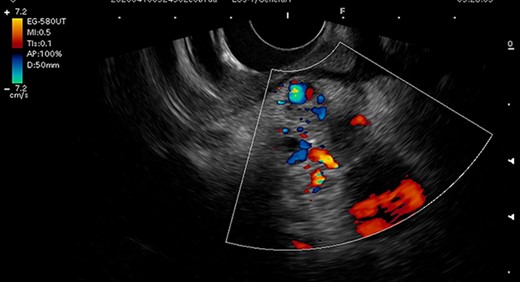

A 54-year-old man was admitted to our hospital presenting with acute upper abdominal pain. He had no family history of pancreatitis, hereditary disease or abdominal trauma; however, he had a history of habitual alcohol consumption. Blood tests showed an elevated white blood cell count (16 900/μl), serum amylase (260 U/l) and lipase (337 U/l). Contrast-enhanced computed tomography (CT) revealed meandering vessels in the pancreatic head. These vessels were enhanced in both the arterial and portal phases, while the portal vein was enhanced in the arterial phase. Swelling of the pancreatic head suggested the development of pancreatitis (Fig. 1). Three-dimensional CT revealed blood vessel communications between the arteries and veins in the pancreas (Fig. 2). Endoscopic ultrasonography (EUS) also revealed meandering vessels in the pancreatic head surrounded by low echoic lesions with diameters of 8 mm (Fig. 3). Magnetic resonance imaging (MRI) revealed flow voids and a cyst measuring 8 mm in diameter at the pancreatic head. Neither stenosis nor dilation of the main pancreatic duct was observed.

Endoscopic ultrasonography image. Endoscopic ultrasonography showed tortuous vessels and low echoic lesions in the pancreas head, and no findings suspicious of malignancy.